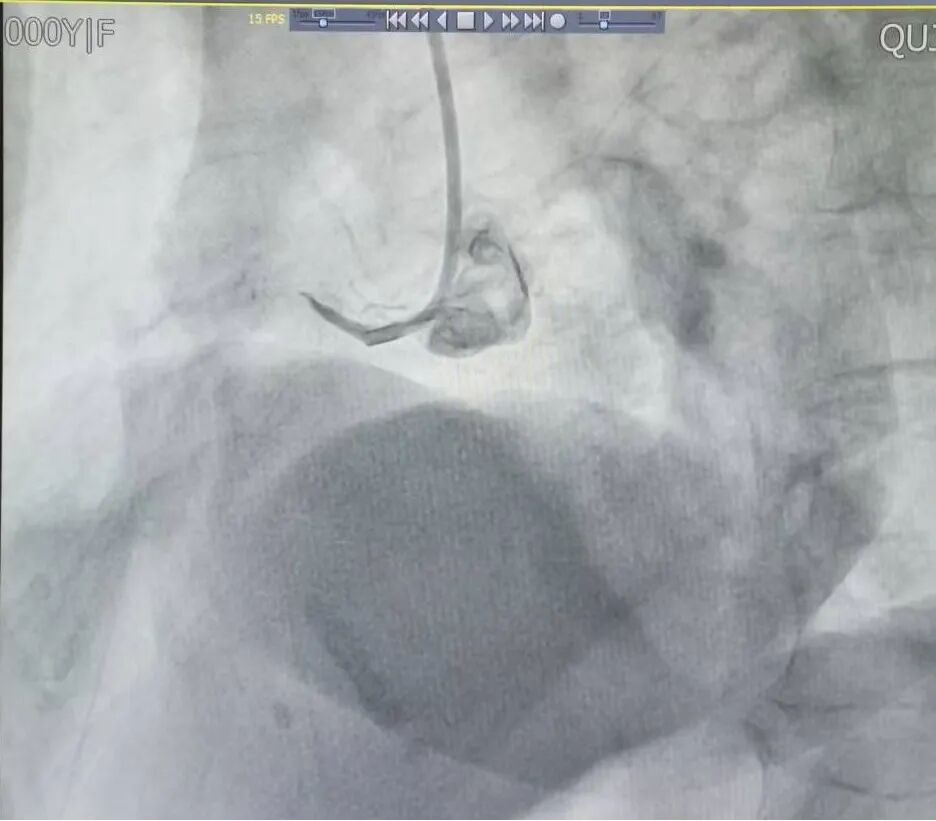

97岁高龄急性心梗获救!急诊PCI再创生命奇迹

近日,云南省曲靖中心医院心血管团队凭借精湛医术与无畏担当,成功为一名97岁高龄急性心肌梗死女性患者实施急诊PCI手术。面对超高龄、高风险、高难度的多重挑战,医护人员争分夺秒、与死神赛跑,最终患者顺利康复出院,创造高龄危重心梗救治的生命奇迹,彰显医院守护百姓健康的初心与实力。

3月23日,罗平县阿岗镇97岁老人黎某突发剧烈胸痛、面色苍白,家属紧急送往云南省曲靖中心医院救治。时间就是生命,医院接诊后迅速启动胸痛中心绿色通道,快速确诊为急性下壁心肌梗死。此时老人心肌持续缺血坏死,病情十分凶险,保守治疗不仅疼痛难以缓解,还极易诱发恶性心律失常、心力衰竭、心源性休克等严重并发症,预后极差。家属全力支持手术救治,这份信任成为医护人员迎难而上的强大动力。

97岁高龄患者实施急诊介入手术,在临床中属于极高风险挑战。患者年事已高,脏器功能衰退,血管钙化严重、脆弱迂曲,术中稍有不慎就可能出现血管损伤、心包填塞、血栓事件等致命风险;术后出血、感染、脏器功能衰竭等并发症概率也远高于普通患者,预后充满不确定性。对手术团队而言,每一步操作都如履薄冰,这不仅是技术上的严峻考验,更意味着巨大的责任与职业压力。但医者仁心,面对垂危生命和家属的殷切期盼,医护团队没有退缩,在充分评估、周密预案、充分告知风险并获得家属知情同意后,立即开展急诊介入手术。

手术台上,介入团队沉着冷静、精准操作,顺利将导丝通过闭塞病变,成功开通梗死相关血管,恢复心肌灌注,全程患者生命体征平稳,手术圆满成功。术后,医护团队精心制定监护与康复方案,24小时密切观察病情、精准调整用药、悉心照料饮食起居,帮助老人平稳度过危险期,从命悬一线逐步好转直至康复出院。